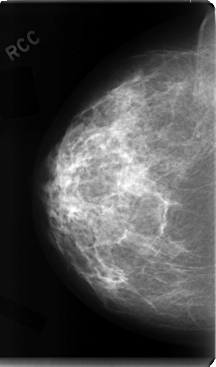

C_0080_1.RIGHT_CC

RIGHT_CC LINES 4760 PIXELS_PER_LINE 2800 BITS_PER_PIXEL 12 RESOLUTION 50 NON_OVERLAY